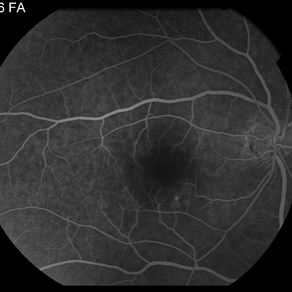

AMPPE

Apr 29 2014 by David W. Faber, MD

24-year-old female presented with central blurry vision for 3-5 days. Vision : OD 20/20, OS 20/100

Photographer: Jodi Schiele, Rocky Mountain Retina Consultants, Salt Lake City, Utah

Condition/keywords: acute multifocal placoid pigment epitheliopathy (AMPPE)